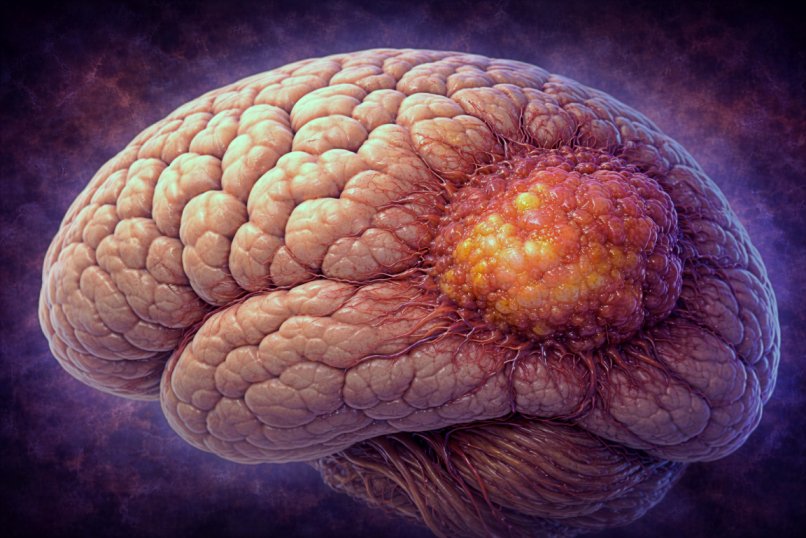

Ce sunt metastazele cerebrale?

Metastazele cerebrale reprezintă cele mai frecvente tumori maligne ale sistemului nervos central. Acestea nu apar din creierul propriu-zis, ci sunt rezultatul diseminării unor celule canceroase de la un alt organ afectat de cancer (cum ar fi plămânul, sânul, rinichiul, melanomul sau colonul). Celulele canceroase migrează prin sânge, se opresc la nivelul creierului și încep să formeze tumori secundare.

Celulele canceroase se desprind din tumora primară, pătrund în vasele de sânge și călătoresc spre creier. Acolo, ele trec de bariera hemato-encefalică – o structură protectoare care apără creierul de substanțe toxice – și încep să se multiplice. De cele mai multe ori, metastazele apar în zona joncțiunii dintre substanța albă și cea cenușie, unde fluxul sanguin este bogat și viteza de circulație este mai redusă.

Metastazele cerebrale apar frecvent în emisferele cerebrale (80%), mai rar la nivelul cerebelului (15%) sau trunchiului cerebral (5%). Localizarea influențează simptomele și posibilitățile de tratament.